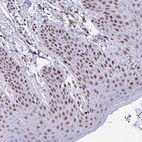

Immunohistochemical staining of human duodenum shows moderate nuclear positivity in glandular cells.